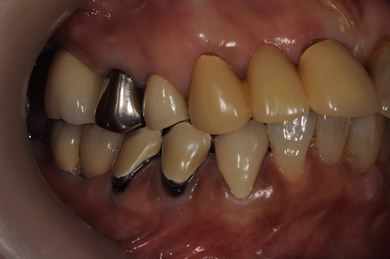

治療前

• 治療前